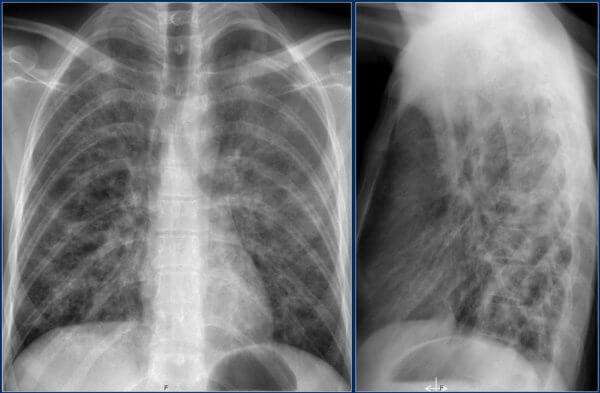

Как отличить бронхит от пневмонии по результатам рентгеновского снимка

пневмония на рентген-снимке: видно почти полное затемнение нижней доли

Несмотря на некоторые различия пневмонии и бронхита, нередко клиника бывает размытой. В такой ситуации для установления верного диагноза необходимо сделать флюорографию или рентгенографию – это наиболее достоверный способ диагностики. По результатам рентгенограммы лечащий врач сможет легко распознать болезнь. Худшие опасения подтвердятся, если на снимке будут отчётливые затемнения.

| Рентген | Усиление лёгочного рисунка | Очаговые затемнения |

Расшифровать данные рентгеновского снимка способен только опытный рентгенолог. Также необходимо знать, что основным рентгенологическим признаком воспаления легких является участок или участки затемнения легочного поля. Однако, здоровые легкие на снимке имеют темный цвет, в то время как затемнения являются белыми участками.

Данной форме характерно формирование больших участков поражения легочной ткани. Патологический процесс может охватывать как одно, так и оба легких. На иллюстрации ниже показана тяжелая форма крупозной пневмонии.